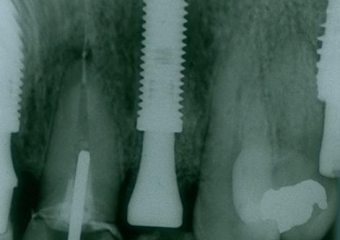

Rx dos implantes Cone Morse instalados

Rx após extração e implantes imediatos nos dentes 12 e 22